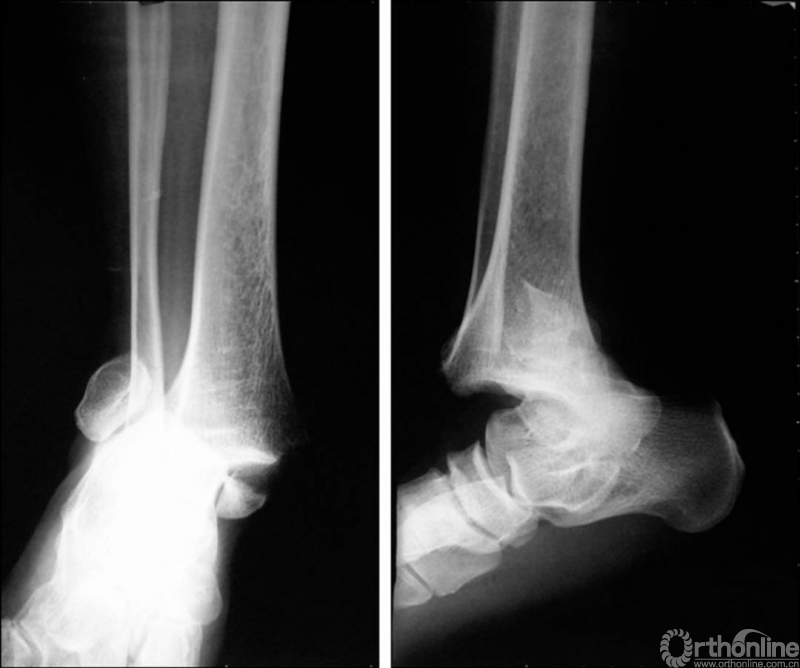

X线诊断:标准的踝关节影像学评估应包括3个位相:前后位(图5),踝穴位(内旋15°)(图6),侧位(图7)。

图5 前后位

图6 踝穴位(内旋15°)

当踝关节严重损伤时内外踝及距骨将发生不同程度的移位(图8)。有时外踝骨折会伴有三角韧带的损伤,静态的X线摄片并不能准确地反映踝关节的稳定性,应力位片及MRI检查可完善对踝关节稳定性及韧带损伤的评估(图9)。此时应通过患肢损伤机制及放射资料准确判断踝关节损伤的类型以正确指导复位和固定。有时单纯内踝骨折可能是更为复杂的“Maisonneuve骨折”的一部分,该骨折还包括腓骨近端骨折及韧带联合损伤,故X线检查应投照整个胫腓骨。

图8 骨折移位明显合并有脱位

图9 应力位X线片(三角韧带断裂)